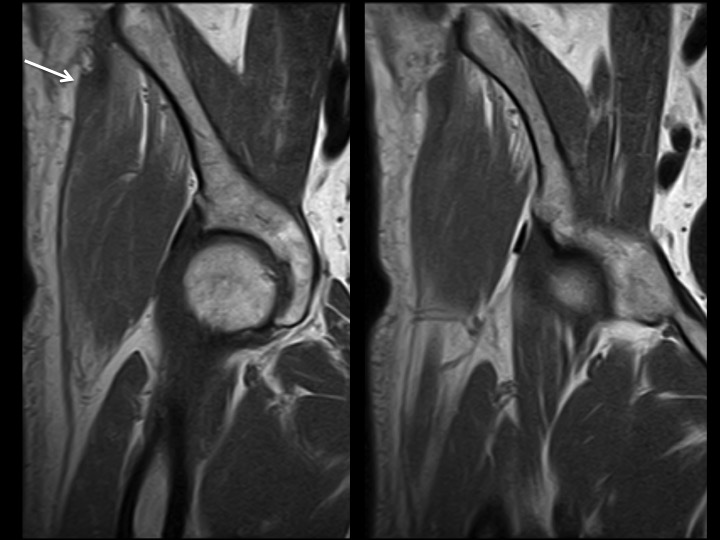

69M 1 week hip pain

There is complete retracted avulsion of proximal iliotibial band at its iliac tubercle origin, with contiguous delaminating tear of the gluteus medius fascia, subfascial hemorrhage and low grade G medius muscle strain. I have only ever seen proximal ITB tears in women, with few non-insertional tears and gluteal fascial tears more common (in my experience) in men. This man has a history of diabetes. I dont know if he had trauma.

iliotibial band ( RID2855 )